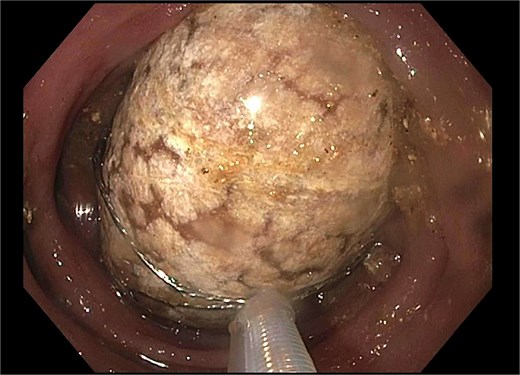

He re-presented 10 days later with nausea, vomiting, and obstipation. CT imaging showed large bowel dilation and a 3–4 cm gallstone lodged in the proximal sigmoid colon (Fig. 2). Flexible sigmoidoscopy confirmed the presence of the stone at a diverticular stricture (Fig. 3). Initial endoscopic retrieval attempts using snare, Roth net, and EHL failed.

Endoscopic view of gallstone impacted at diverticular stricture.

A subsequent attempt with a dual-channel colonoscope allowed for mechanical lithotripsy via trapezoid basket, successfully fragmenting the stone (Figs 4–6). The patient resumed a regular diet, passed flatus and stool, and was discharged with outpatient follow-up for elective cholecystectomy.